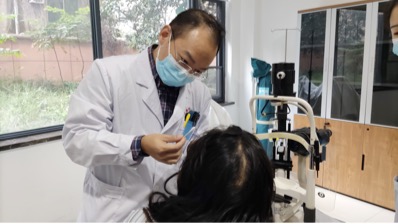

之后,在儿子的安排下,患者连夜赶到武汉艾格眼科医院,泪道与眼眶病科熊士波医生仔细询问受伤过程,以及医治过程,当即和手术团队探讨手术方案,第一步选择合适的麻醉方式,让患者手术台上没有恐惧感、疼痛感。第二步,仔细设计手术方案,选择合适的泪小管内部支撑物,患者已经是伤后 36 小时了,这也许是最后一次修复泪小管的机会。

幸好,所有的努力没有白费,手术历经两小时,非常成功,熊医生终于找到消失不见的泪小管两头,成功吻合,患者再也不用泪流满面。